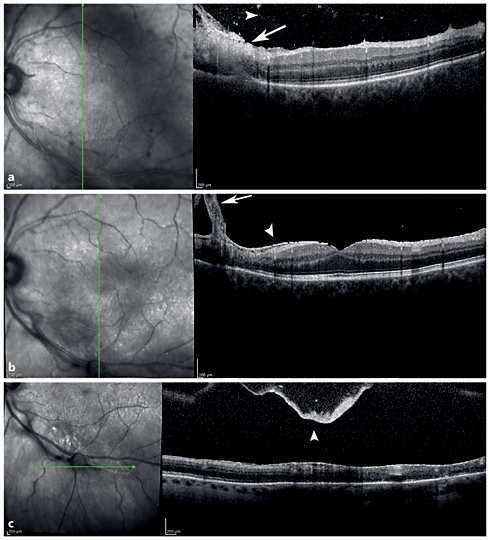

Spectral-domain optical coherence tomography (SD-OCT) imaging is an important diagnostic tool to identify the morphological features of the vitreoretinal changes in ocular toxoplasmosis [39,40,41]. The stage of the disease is determinant for the SD-OCT findings of chorioretinal lesions. Goldenberg et al. [40] studied the vitreoretinal changes of ocular toxoplasmosis, during the acute phase, treatment phase, and after resolution, using SD-OCT. In the acute phase, disruption, thickening, and hyperreflectivity of the neurosensory retina with photoreceptor interruption and retinal pigment epithelial elevation were found. During follow-up, neurosensory retinal layer thinning and disorganization, photoreceptor interruption, and retinal pigment epithelial elevation and/or atrophy were demonstrated. Multiple hyperreflective dots in the vitreous cavity, compatible with posterior vitritis and vitreous cells, and posterior hyaloid thickening with partial detachment were demonstrated in the acute phase. With improvement of disease, hyperreflective dots become smaller, and eventually resolve. The posterior hyaloid may thicken and detach during follow-up. An epiretinal membrane may be found over active as well as scarred lesions (fig. 5).

SD-OCT of a Toxoplasma chorioretinits lesion. a Vertical SD-OCT through the retinal lesion shows retinal thickening with full-thickness retinal hyperreflectivity (white arrow) extending down to the level of the retinal pigment epithelium and Bruch's membrane. Hyperreflective spots in the vitreous (white arrowhead) in the acute phase demonstrate posterior vitreous cell. b Thickening of the posterior hyaloid (white arrow) over the scar and epiretinal membrane formation (white arrowhead) in the chronic phase. c Thickened posterior hyaloid face and a posterior vitreous detachment (white arrowhead) over the lesion in the chronic phase.

SD-OCT of a Toxoplasma chorioretinits lesion. a Vertical SD-OCT through the retinal lesion shows retinal thickening with full-thickness retinal hyperreflectivity (white arrow) extending down to the level of the retinal pigment epithelium and Bruch's membrane. Hyperreflective spots in the vitreous (white arrowhead) in the acute phase demonstrate posterior vitreous cell. b Thickening of the posterior hyaloid (white arrow) over the scar and epiretinal membrane formation (white arrowhead) in the chronic phase. c Thickened posterior hyaloid face and a posterior vitreous detachment (white arrowhead) over the lesion in the chronic phase.